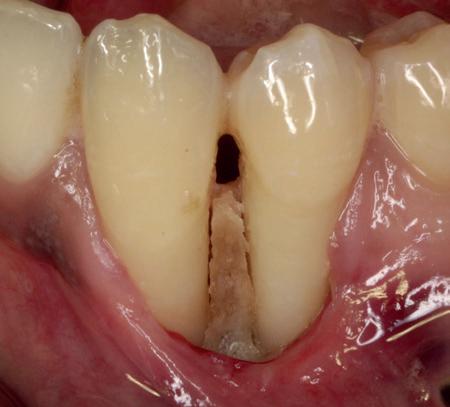

Mevrouw werd naar het Dental Design Center verwezen om een complex probleem aan het bovenfront te beoordelen en indien mogelijk te behandelen. Tien jaar geleden zijn er om esthetische redenen op de 12, 11, 21 en 22 kronen geplaatst. Helaas bleek achteraf een wortelkanaalbehandeling van de 22 noodzakelijk. Na een aantal jaar ontstond er weer een infectie apicaal aan de 22 en werd er een apex uitgevoerd. Helaas had deze behandeling niet het beoogde resultaat. Twee weken voordat ze bij mij op consult kwam, is het element geëxtraheerd en is er een partiële plaat geplaatst als tijdelijke oplossing (foto 1-3).

heeft de nadrukkelijke wens om geen brugconstructie te krijgen. Om die reden is een etsbrug of een conventionele brug geen optie. Daarom bestaat het behandelvoorstel uit vier losse kronen waarvan de 22 implantaat gedragen zal zijn. Een gedetailleerd onderzoek van de regio 22 is noodzakelijk (foto 4-6).

Uit het röntgenonderzoek blijkt dat op de locatie van de 22 veel bot verloren is gegaan en dat er niet direct een implantaat geplaatst kan worden. Om die reden is een botaugmentatie geïndiceerd. Wel zijn distaal van de 21 en mesiaal van de 23 de botpieken aanwezig die de papillen ondersteunen. Naast te weinig bot, is op de locatie 22 in bucco-linguale richting ook te weinig volume gingiva aanwezig. Daarom zal er tevens een soft tissue graft aangebracht worden. Tijdens deze behandeling wordt ook de recessie op de 23 zoveel mogelijk bedekt (foto 7 en 8).